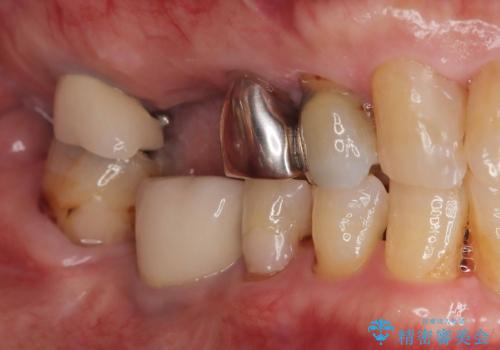

- 虫歯が原因で歯が欠けていました。昔詰めた保険の材料(CR)が劣化しその下が虫歯になっている状態でした。

色々な箇所にCR(保険の材料)を詰めてあったので、CRと虫歯を全部除去した後、オールセラミッククラウンで治療を行いました。

古いCR(保険治療で使用されるプラスチック)を除去すると残りの歯質が薄いため、破折抵抗を考慮しオールセラミッククラウンで治療を行いました。